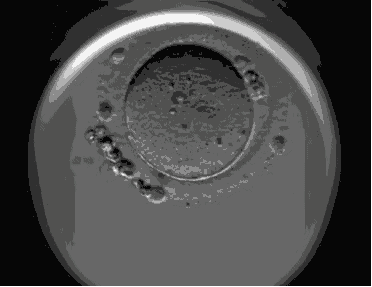

下面是4~8细胞胚胎和囊胚的一个对比???

是不是觉得有点奇怪,在实验室里多呆了2天就成了「种子选手」?